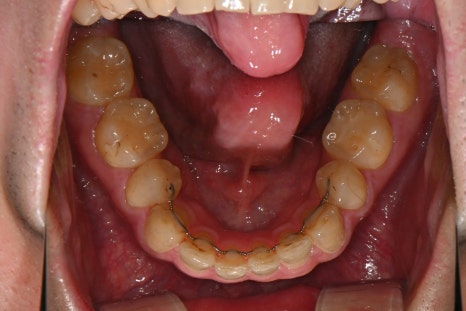

Right photo: The wire on the lower left side has broken, and the retainer on the right side has fallen off completely, creating a gap between the teeth.

Over time, the retainer had weakened and was no longer functioning properly.